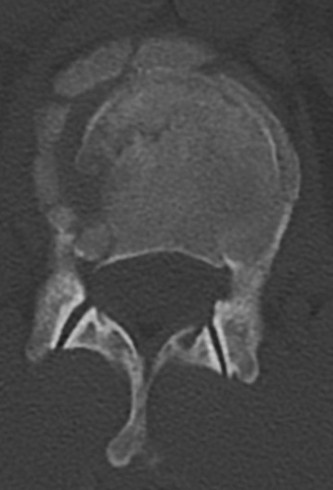

The options for definitive treatment of cervical facet dislocations? CASE 24 A 23-year-old man presents to your emergency room with severe back pain after a 30-foot fall out of a tree while intoxicated 3 hours earlier. He reports no neck pain, no upper extremity weakness or numbness, though he states that he feels weak in his legs and numbness in his groin. Currently, he is awake, alert, oriented, and cooperative and does not appear to be intoxicated. Vital signs included a blood pressure of 100/60 and heart rate of 95 beats per minute. Physical examination demonstrates midline tenderness of the lumbar spine with no palpable gap or step-off. Upper extremities show full strength and sensation. Lower extremities examination shows 2/5 bilateral strength in hip flexion and knee extension, 3/5 bilateral strength of ankle dorsiflexion, big toe extension, and ankle plantar flexion. Rectal tone is normal. Sensation to light touch and pin prick is diffusively decreased in both lower extremities and in the perineum. Bulbocavernosus reflex is present. A CT scan of his cervical and thoracic spine is negative. CT images of his lumbar spine are shown in Figures 1–32 and 1–33.

fractures of the anterior or posterior elements. The hallmark feature is a translation deformity that can be noted by misalignment of the vertebral bodies in the coronal and/or sagittal planes. A lumbar spine MRI is obtained, images from which are shown inFigures 1–34 and 1–35. Based on the information presented, the type of neurological injury is best characterized as which of the following? 1. Cauda equina injury

Figure 1–34

Figure 1–35

The correct answer is (A). The MRI demonstrates the L2 fracture with canal compromise. In this patient, the conus medullaris of the spinal cord terminates at the T12–L1 level. The fracture is at the L2 level. Thus, the neurological injury is at the level of the cauda equina, distal to the conus medullaris and spinal cord. The patient’s neurological examination is consistent with this type of injury with the presence of lower extremity weakness, intact rectal tone, and perineal numbness, though this can vary.